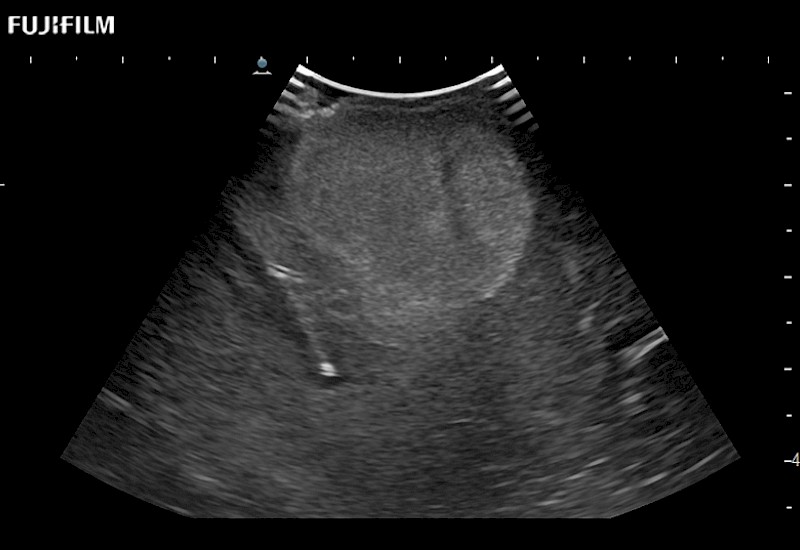

Tight curved (12mm) array transducer that is ideal for scanning during cranial guidance procedures.

Main Specifications:

Smaller footprint (20mm) curved array transducer that is ideal for scanning during cranial guidance procedures.